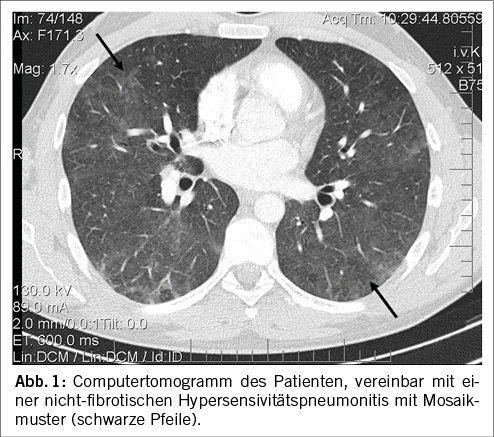

Differentialdiagnostisch zogen wir bei wiederkehrender, anfallsartiger Dyspnoe und Husten ein Asthma bronchiale in Betracht. Die Lungenfunktion zeigte jedoch keine obstruktive, sondern eine leichte restriktive Ventilationsstörung (TLC 75%Soll) mit einer grenzwertig tiefen CO-Diffusionskapazität. Die Oxygenation war in Ruhe dank leichter Hyperventilation knapp suffizient (PO2 70 mmHg, SpO2 95%, PCO2 33 mmHg). Unter mittelschwerer Belastung (100 Watt) bestand eine signifikante Arbeitshypoxämie (PO2 58 mmHg, SpO2 90%, PCO2 32 mmHg). Eine infektiöse Ursache erschien bei Symptompersistenz trotz antibiotischer Therapie und tiefen Entzündungswerten unwahrscheinlich. Zur weiteren Beurteilung wurde ein CT-Thorax durchgeführt, in welchem beidseitige, basal betonte milchglasartige Trübungen des Lungenparenchyms zur Darstellung kamen (Abbildung 1). In Zusammenschau der klassischen Anamnese mit zunehmendem Reizhusten und abendlicher Malaise, dem klinischen Bild mit bilateralen inspiratorischen Rasselgeräuschen, wie auch der restriktiven Ventilationsstörung und den Charakteristika einer interstitiellen Lungenerkrankung in der Bildgebung wurde der Verdacht einer HP – bei Tätigkeit als Landwirt entsprechend einer HP Typ Farmerlunge – gestellt.

Als bildgebendes Verfahren wird ein High-Resolution-CT (HRCT) empfohlen, welches bei typischen Befunden eine sichere Unterscheidung zwischen nfHP und fHP zulässt. Bei weiterhin unklarer Diagnose wird auf Befunde aus BAL und transbronchialer Biopsie zurückgegriffen. Typische Befunde aus diesen Modalitäten sind in Tabelle 1 ersichtlich [5].